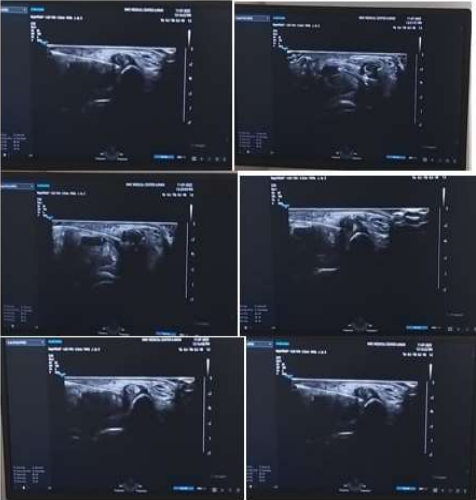

FIG 1. Median Nerve Hydrodissection(HD) at The Wrist Under Ultrasound Guidance.

Figure 2, Figure 3, Figure 4, Figure 5

TOTAL 4 ULTRASOUND GUIDED MEDIAL NERVE HYDRODISSECTION FOR CARPAL TUNNEL SYNDROME WERE DONE BETWEEN JULY 2023- JANUARY 2024.

Technique  used – method 1

Linear probe, high frequency.

25 g needle 1.5” length

Syringe 5 and 10 ml

20-50 ml 5% dextrose

2% lidocaine

Dressing

STEPS-

NERVE IDENTIFICATION- I usually start from proximal to distal from the forearm identifying the nerve ( honey comb appearance) in the forearm and then trace it distally into the carpal tunnel in the wrist.

The nerve is easy to find proximally in the forearm due to absence of any tendons and clarity of the structure within the forearm MUSCLES.

A 360 degree dial needle placement and injectate injection is done to free the nerve from the adhesions all around as shown in the diagram and USG  pictures.

Figure 6, Figure 7, Figure 8

Figure 6

Figure 7

Figure 8